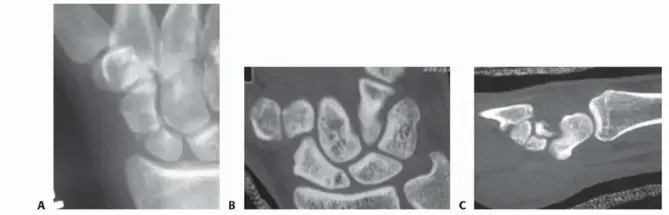

- المتابعة: يتم إجراء أشعة سينية دورية (X-rays) لمراقبة عملية التئام الكسر والتأكد من عدم حدوث أي تشريد. قد يطلب الدكتور هطيف أحياناً تصويراً متقدماً مثل التصوير المقطعي المحوسب (CT scan) لتأكيد التئام العظم، خاصة قبل رفع الجبس.

بمجرد أن يقرر الدكتور هطيف أن الكسر قد التئم بما فيه الكفاية، إما عن طريق الأشعة السينية أو الأشعة المقطعية، سيتم إزالة الجبس أو تخفيف الحماية. هذه هي اللحظة التي تبدأ فيها العمل الجاد لإعادة التأهيل.